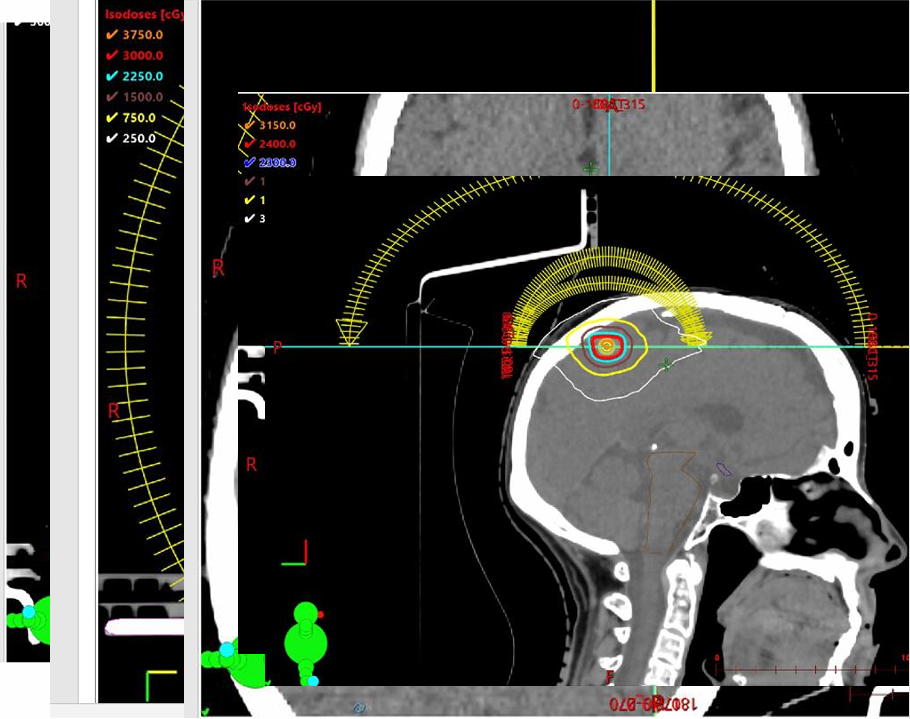

中枢神经系统(CNS)受累:2022年7月,患者出现言语困难。MRI发现左额叶单发巨大脑转移瘤,伴严重血管源性水肿及中线移位。

外科手术:于7月22日行急诊手术切除。

放射外科:8月对切除残留腔实施SRT,27Gy/3次。

ee67d7ea-efa1-4955-83e4-1454ba061da1.png

2023年初,病情进一步恶化,MRI显示多发脑膜及实质转移。患者拒绝医生建议的靶向药物Adagrasib,继续依赖顺势疗法。在此期间,针对不断出现的脑部病灶,医疗团队实施多次精准放疗(SRS/SRT),包括枕叶、额叶及蝶骨病灶。